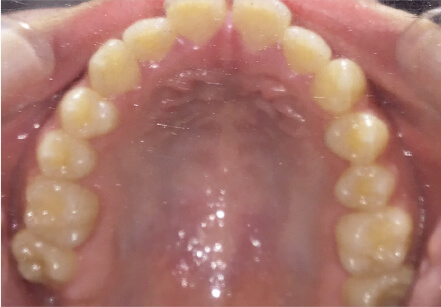

叢生の症例

8歳

/

女性

相談内容

前歯がでている、前歯が噛み合っていない

カウンセリング・診断結果

上下叢生、顎が狭いのでクリアコレクトで拡大配列+トレーニングで進めてく

治療内容・方法

全額アライナー矯正 クリアコレクト

術後の経過・現在の様子

リンガルアーチ使用

治療のリスク

痛み・歯根吸収・歯肉退縮・虫歯・後戻り

費用・治療期間

924,000円、8ヶ月

トレーニングなど